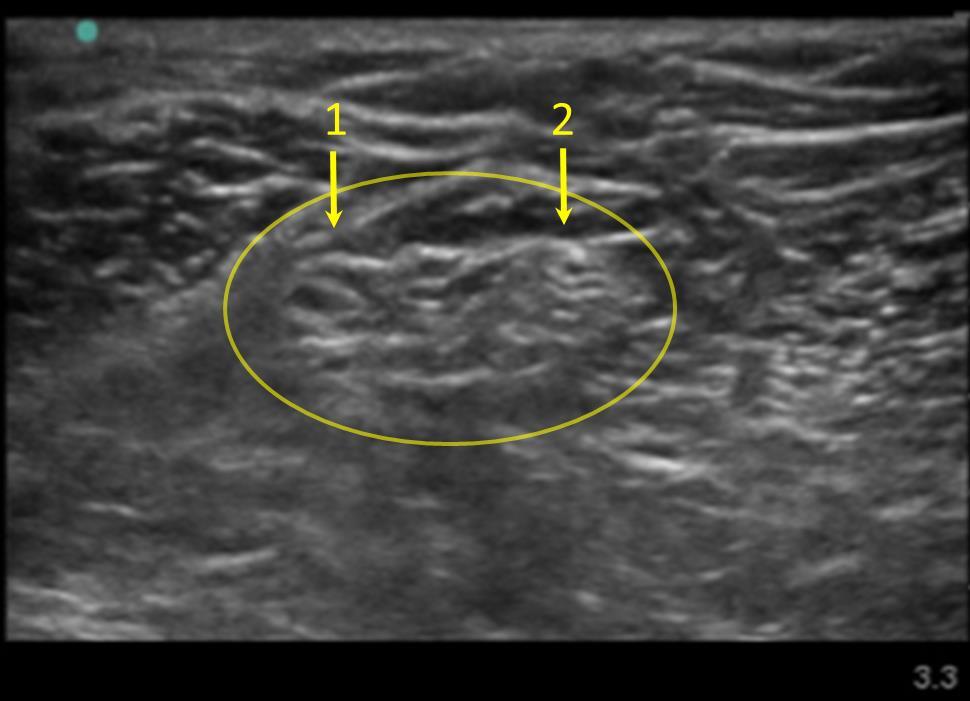

膝窩坐骨神経分岐 2 イメージ

総腓骨神経

脛骨神経